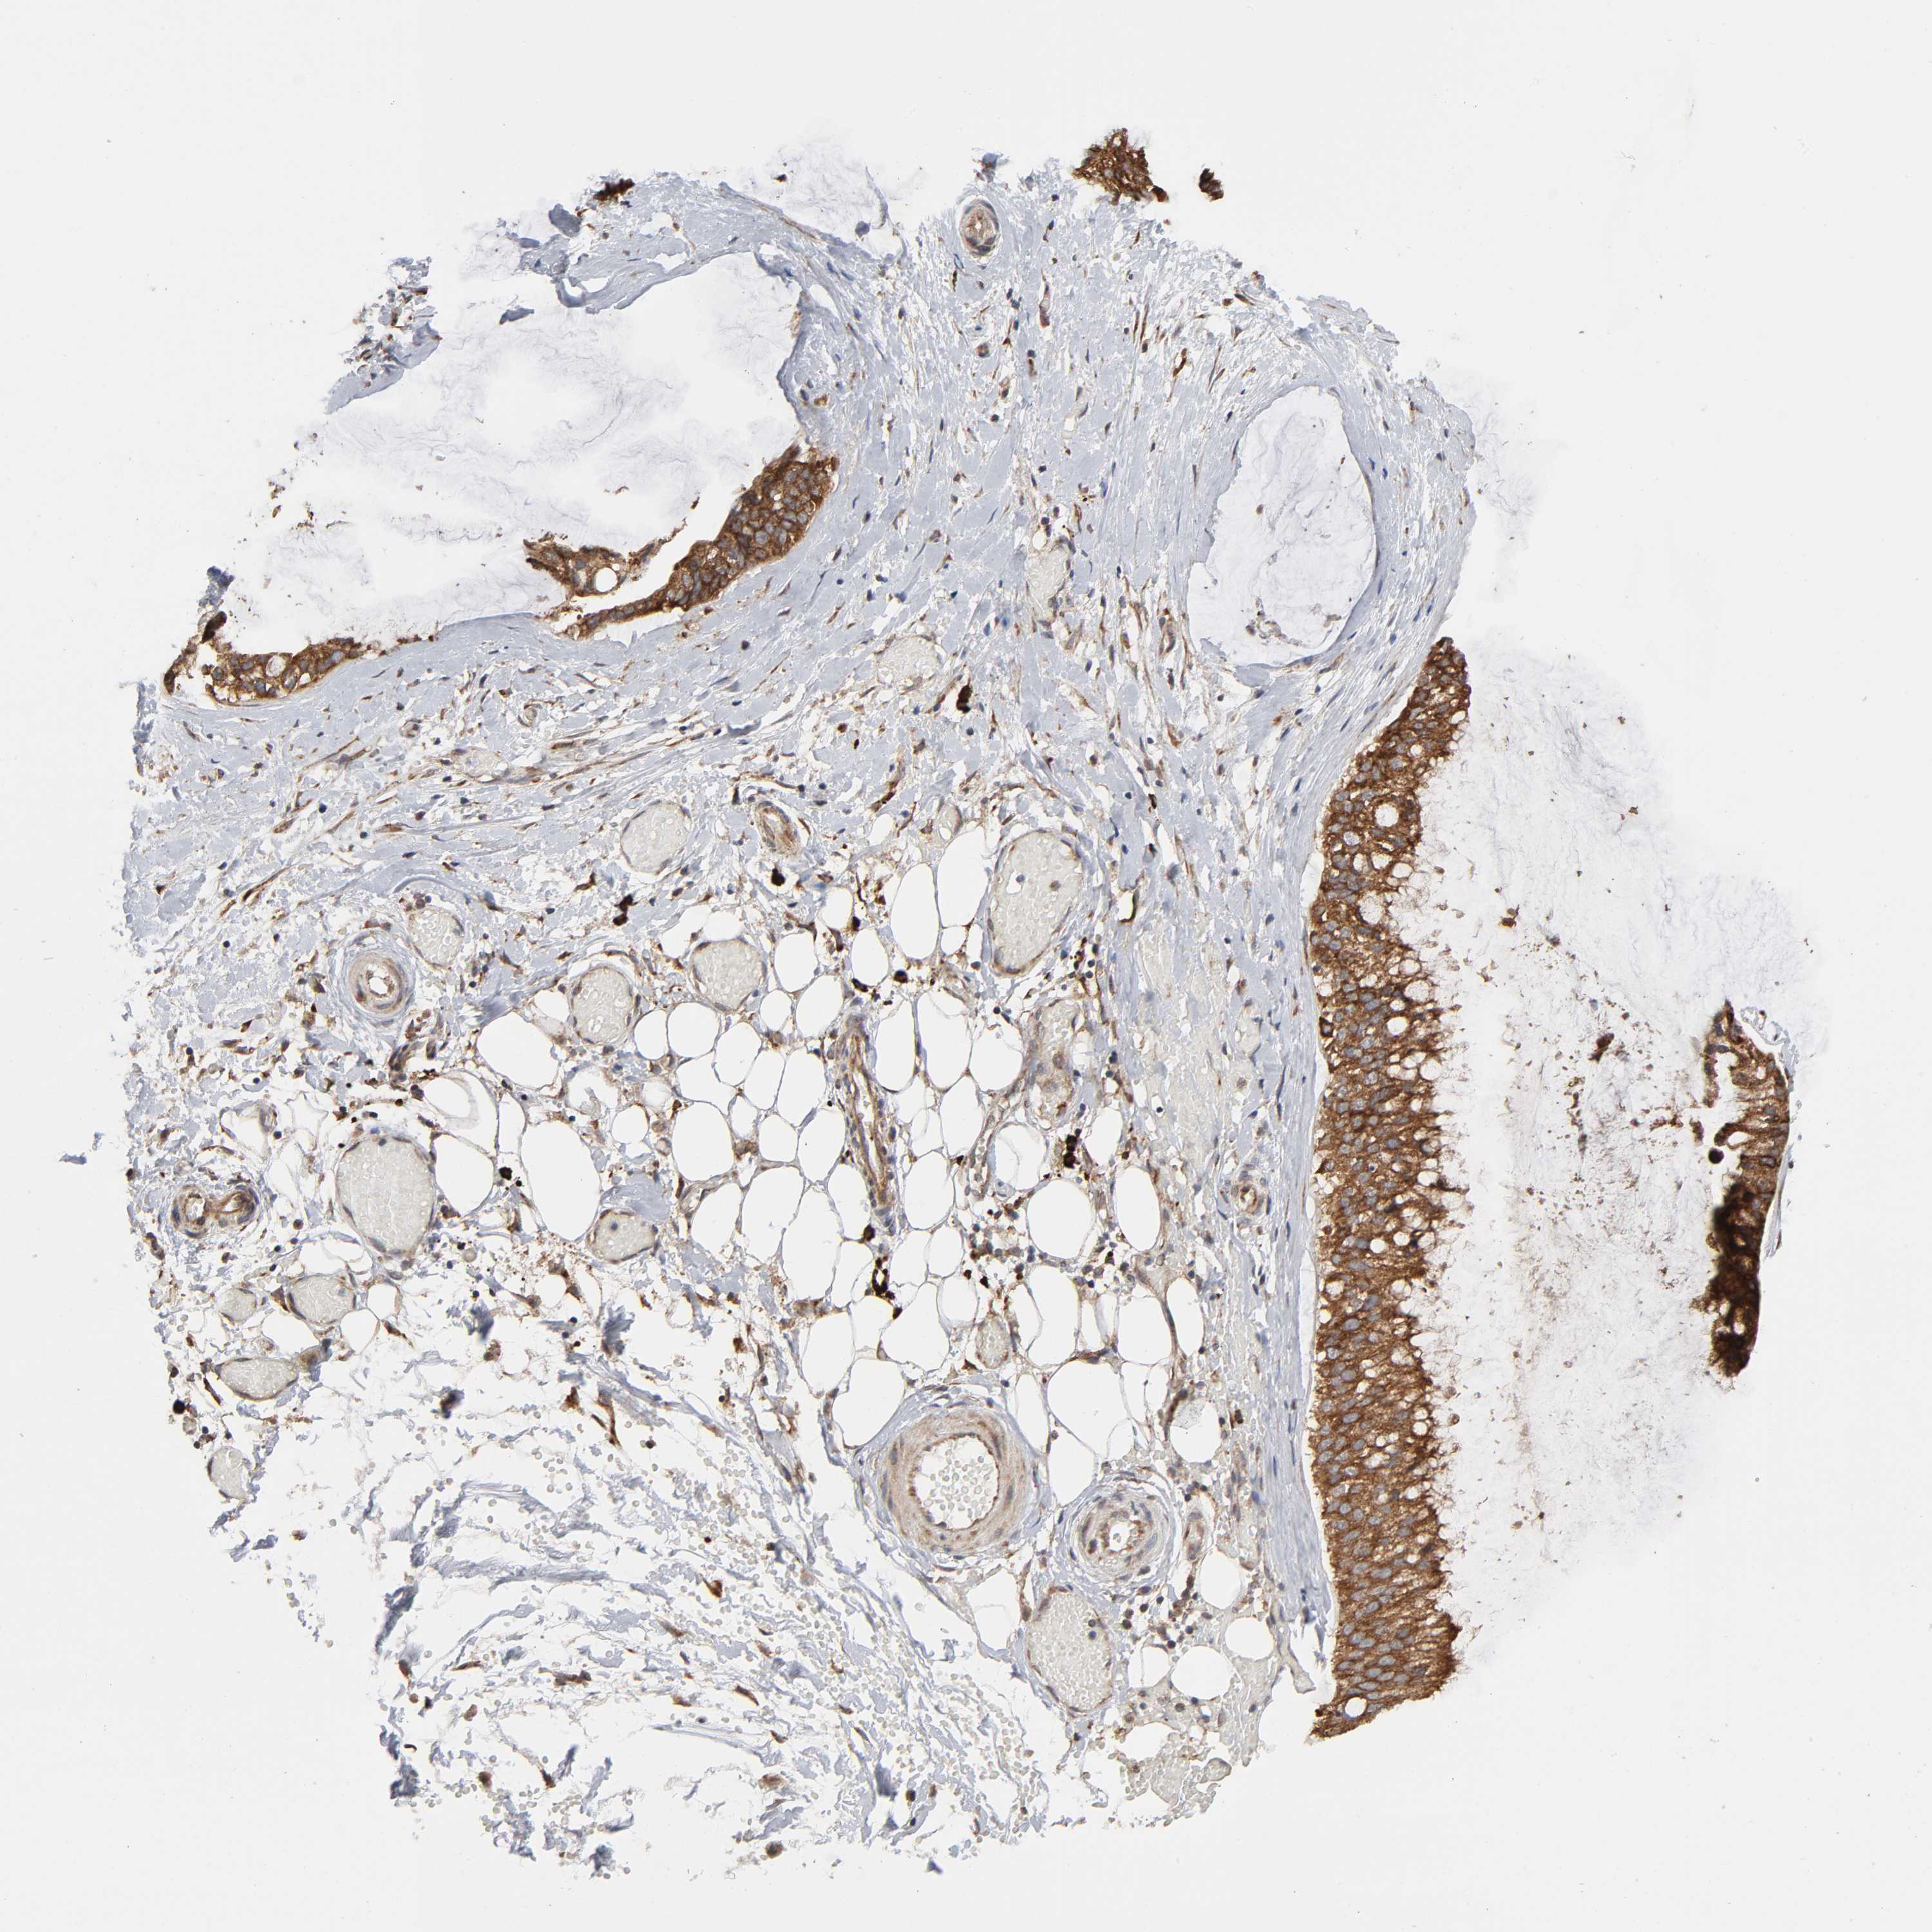

OVARIAN CANCER - Protein expressioni

A mouse-over function shows sample information and annotation data. Click on an image to view it in a full screen mode. Samples can be filtered based on level of antibody staining by selecting one or several of the following categories: high, medium, low and not detected. The assay and annotation is described here.

Note that samples used for immunohistochemistry by the Human Protein Atlas do not correspond to samples in the TCGA dataset.

Antibody stainingi

Antibody staining in the annotated cell types in the current human tissue is reported as not detected, low, medium, or high, based on conventional immunohistochemistry profiling in selected tissues. This score is based on the combination of the staining intensity and fraction of stained cells.

Each image is clickable and will lead to virtual microscopy that enables deeper exploration of all samples and also displays staining intensity scores, fraction scores and subcellular localization as well as patient and tissue information for each sample.

Antibody HPA004014

Staining

High

Medium

Low

Not detected

Intensity

Strong

Moderate

Weak

Negative

Quantity

>75%

75%-25%

<25%

None

Location

Nuclear

Cytoplasmic/membranous

Cytoplasmic/membranous,nuclear

Cystadenocarcinoma, serous, NOS

Cystadenocarcinoma, mucinous, NOS

Carcinoma, endometroid